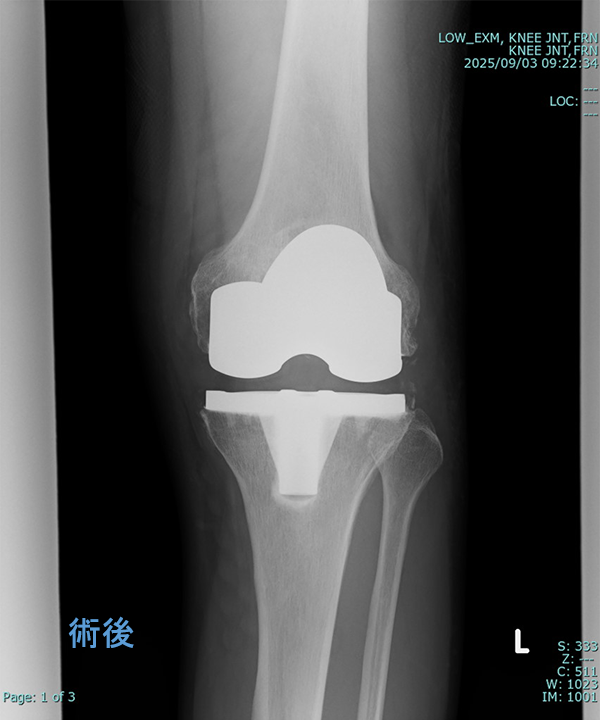

変形性膝関節症に対する手術

◆人工膝関節全置換術

(Total Knee Arthroplasty:TKA)

入院期間 3~4週間

外来リハビリ 2~3か月

術後